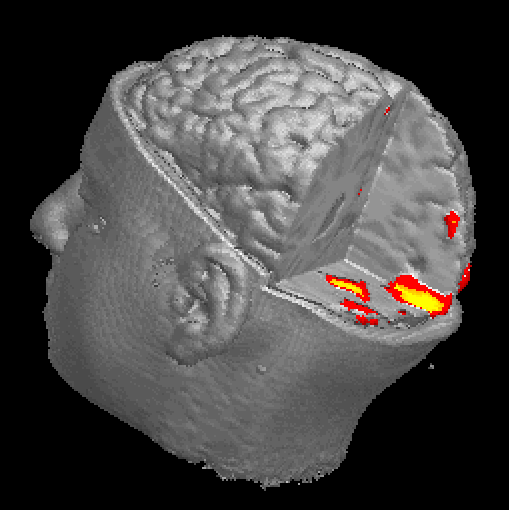

篇科学论文中,而且这个数字至今还在以每周30至40篇的速度增长。人们之所以对它如此重视,那是因为比起现有其他大脑功能成像技术,fMRI在“观察活动中的大脑”时,不仅时间分辨率更高,就连空间分辨率也可达到毫米水平。借助fMRI,对大脑的研究便可扩展至记忆、注意力、决定……在某些情况下,fMRI技术甚至能够识别研究对象所见到的图像或者阅读的词语。对个人内心世界的这些揭示不禁让人期待在大脑中鉴别谎言这种复杂状态的可能性。

人脑是人体最重要的器官之一,对于人脑功能的探求无疑是非常有意义的事情。长久以来,科学家们就注意到这样的事实: 即人脑的功能反映在大脑皮层是按空间分区的,在脑内次级结构也是按空间分隔的。研究脑功能映射(Function Brain Mapping)有许多成功的模式(Modality),例如正电子发射断层扫描(Positron Emission Tomography,PET),在向脑内注射15O水后,通过测量局部脑血流(rCBF)的方法来检测大脑的活动。脑电图(EEG)和脑磁图(MEG)也可检测大脑对诱发刺激响应的电或磁信号,但很难对活动区作准确的空间定位。也有人用光学的方法检测脑功能。例如近红外光谱仪和基于可见光的时间分解反射光谱仪,都是基于检测神经活动引起的脑血流和代谢改变。在众多的模式中,用于脑功能定位的磁共振成像(Magnetic Resonance Imaging,MRI)技术,或曰功能磁共振成像(Functional MRI)是一种非常有效的研究脑功能的非介入技术,已经成为最广泛使用的脑功能研究手段。最早起源于1991年春天,美国麻省总医院(Massachusetts General Hospital,MGH)的磁共振研究中心利用磁共振成像生成反映脑血流变化的图像。它虽然是一种非介入的技术,但却能对特定的大脑活动的皮层区域进行准确、可靠的定位,空间分辨率达到1mm,并且能以各种方式对物体反复进行扫描。

fMRI的另一个特点是,能实时跟踪信号的改变。例如在仅几秒钟内发生的思维活动,或认知实验中信号的变化。时间分辨率达到1s。大批的脑科学研究人员已经开始从事磁共振功能神经成像的研究,并将它应用于认知神经科学。医学领域的迫切需求也进一步促使fMRI技术的发展,一些在病理方面的应用已初见端倪,例如利用扩散(Diffusion)成像和灌注(Perfussion)成像技术对大脑局部缺血进行诊断等。本文着重介绍功能磁共振的原理及应用方面的现状和前景。